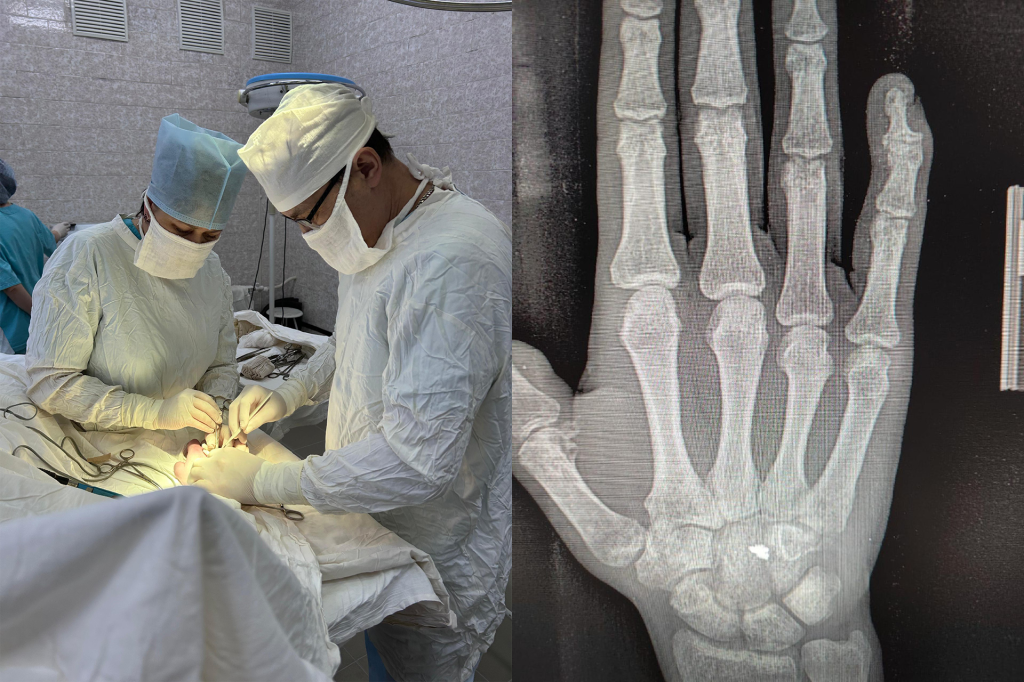

В Башкирии хирурги удалили военнослужащему осколок гранаты

Врачи Верхне-Татышлинской больницы в Башкирии провели успешную операцию по удалению осколка гранаты участнику спецоперации. Об этом рассказали в Минздраве региона.Ранение мужчина получил от разорвавшегося всего в нескольких метрах снаряда. Осколок гранаты попал в область сухожилия мышцы разгибателя пальцев. Инородное тело вызывало резкую боль и ограничивала движения кисти.

«Хирурги Верхне-Татышлинской ЦРБ целиком и полностью извлекли осколок. Теперь солдат сможет вернуться к своим боевым обязанностям», — написали в пресс-службе Минздрава. Теги: